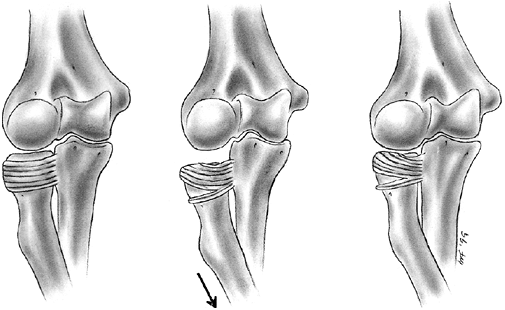

nerve function. Neurovascular problems are frequent, and fracture

management may be altered if neurovascular compromise is present. In

the absence of neurovascular compromise, displaced fractures can be

splinted and managed safely in a delayed manner as long as the child is

closely monitored (132,133). Primary CRPP is the preferred treatment for type III injuries (134) (Fig. 33.18).

Displaced supracondylar fractures treated by closed reduction and

casting have a higher incidence of residual deformity than those

treated with reduction and pinning (134). Closed reduction and casting also has a higher risk of Volkmann ischemic contracture than treatment with early pinning (134).

experience has demonstrated that two or three laterally placed pins are sufficient for stabilization (137).

The authors prefer laterally placed pins without a medial pin except in

unusual circumstances. When a medial pin is used, one should be aware

that extreme elbow flexion could result in ulnar nerve subluxation from

its groove and increase the risk of damage during pinning. When

possible, it is advisable to place the lateral pin first to provide

provisional stability so that the medial pin can be inserted with the

elbow in less than full flexion, placing the ulnar nerve farther

posterior. It is also advisable to make a small incision over the

medial epicondyle and dissect with a hemostat, so that the medial pin

can be placed directly on the bone. Anatomic alignment is preferred,

but this may be difficult to achieve in some cases. When the quality of

reduction is in doubt, comparison radiographs of the opposite elbow can

be obtained intraoperatively. The Baumann angle should be within 5 to 8

degrees of the angle on the contralateral side. As long as fixation is

secure, it is the author’s opinion that one may accept up to one-third

translation of the distal fragment, 30 degrees of malrotation, and 20

degrees of extension after pinning (capitellum anterior to the anterior

humeral line). Initial immobilization should be in a nonconstrictive

splint or cast with the elbow in less than 90 degrees of flexion. The

authors prefer a cast that has been bivalved and spread with the elbow

in approximately 70 degrees of flexion. Oral analgesics are usually

sufficient for pain relief. The need for intravenous narcotics may

indicate ischemia. Immobilization is continued for 3 to 4 weeks, at

which time the pins are removed and active range of motion is initiated.

![]() |

|

Figure 33.18 Type III supracondylar humerus fracture. A: This type III fracture demonstrates lateral displacement. B:

The lateral projection also shows flexion of the distal fragment. The treatment of this less common position is the same as that for extension fractures. The posterior periosteum is torn, and hyperflexion of the elbow will excessively forward-flex the distal fragment. The elbow is best pinned at slightly less than 90 degrees of flexion, because it is technically difficult to pin the elbow in extension. C and D: Anteroposterior and lateral postreduction and pinning films. |

reduction through a medial approach, adding a lateral incision, if

necessary. An anterior surgical interval can also be used, and is

recommended if the neurovascular structures need to be exposed. The

posterior approach should

be

used cautiously because it disrupts any remaining intact soft tissue

and may disrupt the primary vascular supply to the distal humeral

fragment (122,123).

Complete vascular disruption is uncommon, because the thick local

muscle envelope protects the artery. Vascular evaluation after

reduction requires differentiation of the pulseless extremity that is

pink and viable from one that is cold and pale with vascular

insufficiency. The child who has a well-perfused hand but an absent

radial pulse after satisfactory closed reduction does not necessarily

require routine exploration of the brachial artery (129,138,140,141).

The pulse usually returns within 48 hours. Likewise, the absence of a